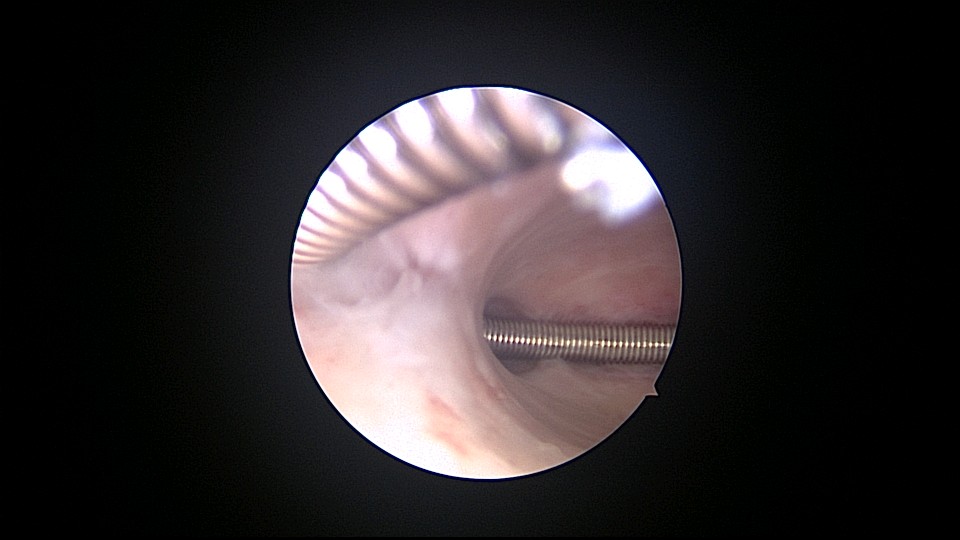

患者56岁,G4P1,顺产1次。1990、1991、1992年三次安环,均自然脱落,1993年第4次安环至今,共31年。现绝经4年,外院取环失败。患者阴道、宫颈、子宫萎缩,宫颈外口无法夹持,探针、中弯钳均无法打开宫颈外口,一筹莫展多时。最后用缝线缝住宫颈11点位及1点位,牵拉宫颈,尖刀片十字切开宫颈外口,B超监护下宫腔镜艰难进入宫颈管,见宫颈管封闭粘连,宫颈内口左侧粘膜下肌瘤遮挡视野。多次努力,镜子成功进入宫腔,见O型环两侧与子宫肌壁嵌顿,异物钳牵拉几次失败,用取环钩钩取,多次尝试终于成功钩住环,牵拉到宫颈外口,用中弯钳取出节育环,环变形,宫壁见节育环割裂痕迹,宫腔少许积血,无其他异常。